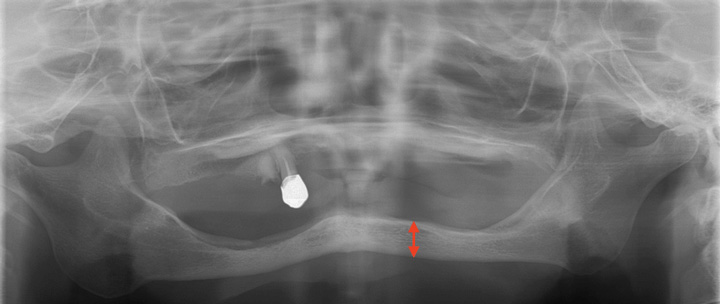

下の二つのレントゲンを比較してみます。

赤の矢印の長さに注目してください。これは下顎の骨の厚みです。この骨の上の歯ぐきに入れ歯が乗ります。この骨の厚みがあるほど、しっかりした土台になり、入れ歯が安定します。逆に、骨の厚みがないということは、土台がないということになるので、入れ歯は食事のたびに動くことになり、動くたびに歯ぐきを傷つけてしまいます。

土台の状態以外にも、口の周りの筋肉、舌の筋肉のバランスによっても入れ歯の安定性は大きく異なりますので、入れ歯を新しく作る際には、適切な診査と処置が必要になります。